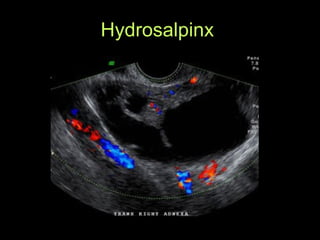

Hydrosalpinx